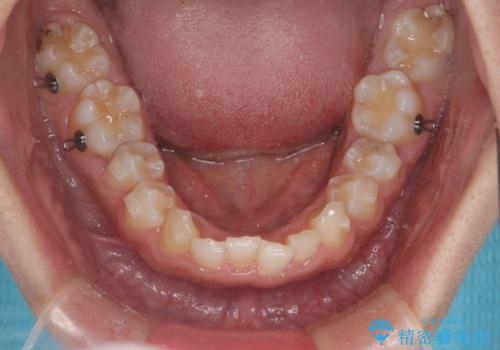

- 患者様は、ディープバイト(深い噛み合わせ)と、咬合平面の左下がりが気になるとのことでご来院されました。診断の結果、非抜歯で治療可能と判断し、透明なマウスピース型矯正装置「インビザライン」を用いる方針としました。治療では、歯列全体の調整を行いながら、咬合平面の水平化を重点的に進める計画を立案しました。2年間で計画的にマウスピースを交換し、左右のバランスと噛み合わせの改善を目指しました。

ディープバイトの矯正は、噛み合わせが深くなりがちなため、細心の注意を払いながら進める必要があります。本症例では、奥歯の高さを調整しつつ前歯の噛み合わせを浅くすることで、全体の咬合バランスを整えました。また、咬合平面の左下がりを修正する過程で、歯列に不均等な力がかからないよう、インビザラインのアタッチメント配置を最適化しました。患者様には装着時間を守っていただき、治療が計画通り進むよう協力をお願いしました。治療終了後には、リテーナーを装着して安定性を確保しました。